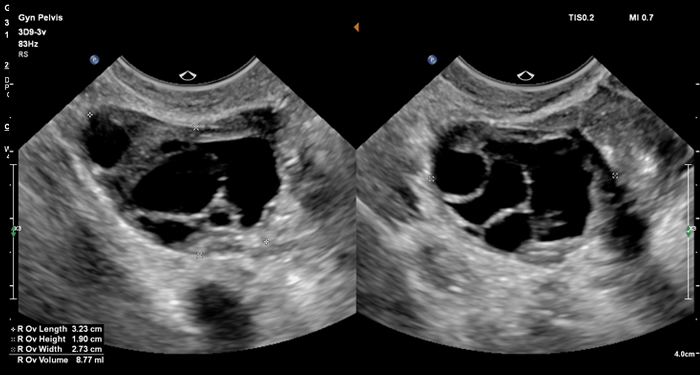

At the touch of a button, the new MaxVue high-definition display brings extraordinary visualisation of anatomy with 1,179,648 additional image pixels compared to a standard 4:3 display format mode. MaxVue enhances ultrasound viewing during interventional procedures and provides 38% more viewing area to optimise the display of dual, side/side, biplane, and scrolling imaging modes.

MaxVue offers a 38% greater viewing area.